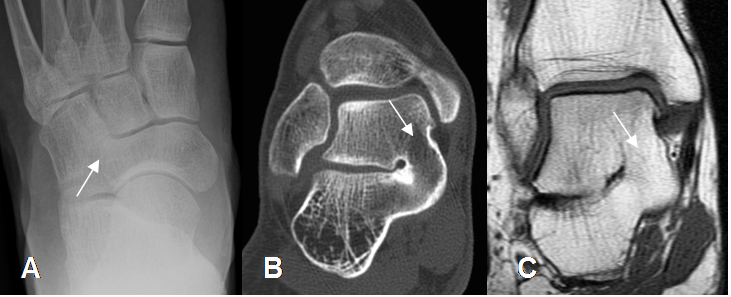

Fig 135 B. Coalición ósea del tarso.

A: Rx AP. Fusión y formación de puente óseo entre el escafoides, cuboides y la cuña lateral.

B: TAC coronal y C: RM T1 coronal. Coalición ósea talocalcánea, en la parte medial.